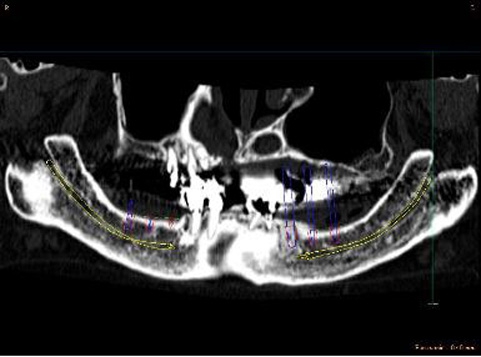

ショートインプラント

術前術前骨の高さが不足している場合、通常のインプラントでは処置が不可能なものが多い。特殊なショートインプラントを用いて可能になる例。 術前 術前CT像術前CT像術前CT像、下歯槽神経が下あごの中央部を走行しているため利用できる骨の高さが少ない。 埋入予定計画埋入予定計画埋入予定計画 術後レントゲン術後レントゲン、ひだりは少し神経をおそれすぎてやや埋入深度が不足、しかしこれでもしっかりと骨と固着した。